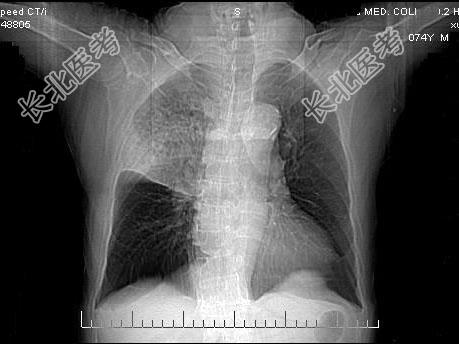

- 单项选择题男,23岁, 高热,咳铁锈色痰, 胸部CT扫描如图,最可能的诊断为 ( )

A、右上肺干酪性肺炎

B、右上肺金葡菌肺炎

C、右上肺大叶性肺炎

D、右上肺中央型肺癌

E、右上肺肺结核